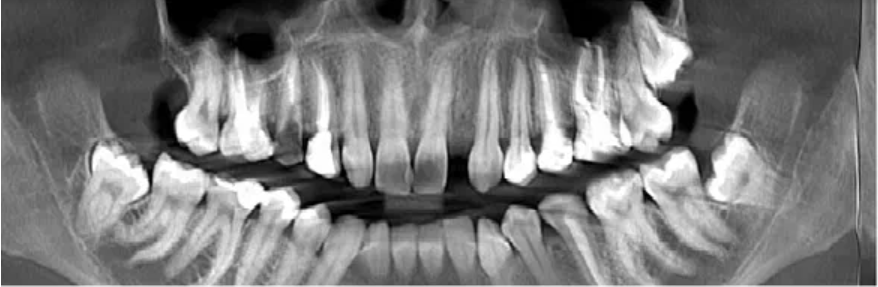

Мы провели Анастасии первичный осмотр и сделали КТ, чтобы оценить сложность будущего удаления. И вот что мы увидели👇

КТ Анастасии

Под удаление у пациентки идут зубы 2.8, 3.8 и 4.8. Все эти «восьмерки» ретинированные и дистопированные👇

Зубы под удаление

Ситуация Анастасии достаточно сложная. Ее зубы располагаются очень глубоко внутри толщи кости.